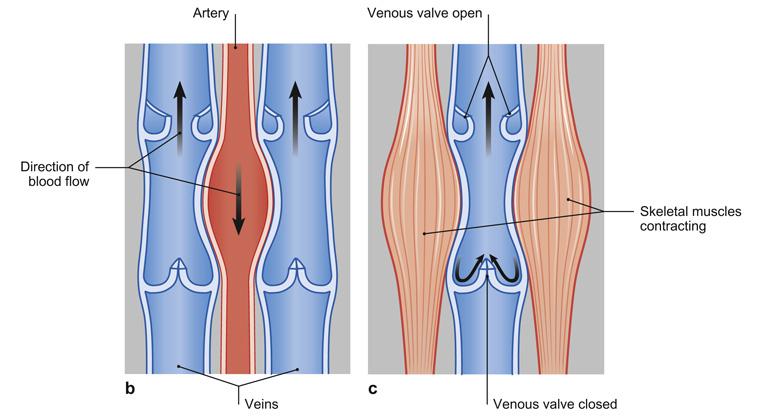

Fig 3.47: Kleppensysteem in de venen

kleppen spieren -

kern van bindweefsel in klep

endotheel elastinevezels (rood) elastine + collageen (groen)

|

|